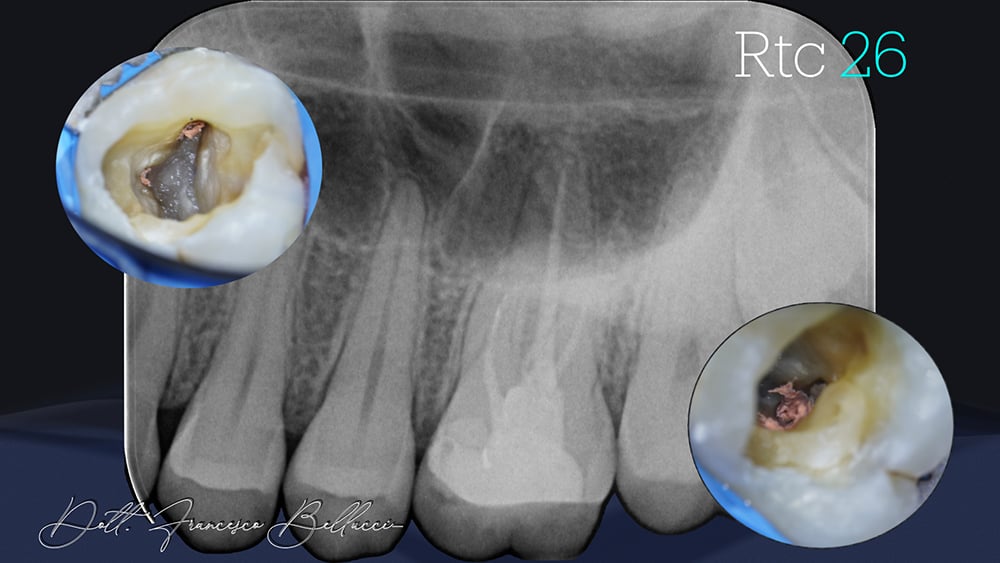

All’esame radiografico si nota una cura canalare non perfettamente congrua, con piccole reazioni periapicali e una anatomia delle radici mesiali con una severa curvatura (Fig. 1).